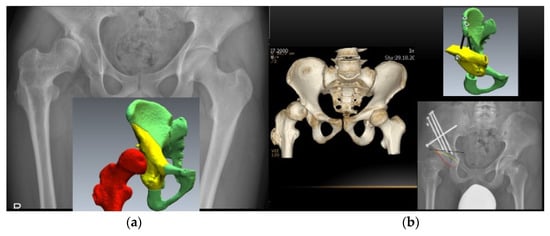

3.5. Hip

- Brumat, P.; Mihalič, R.; Benulič, Č.; Kristan, A.; Trebše, R. Patient-Specific Template and Electromagnetic Navigation Assisted Bilateral Periacetabular Osteotomy for Staged Correction of Bilateral Injury-Induced Hip Dysplasia: A Case Report. J. Hip Preserv. Surg. 2021, 8, 192–196. [Google Scholar] [CrossRef] [PubMed]